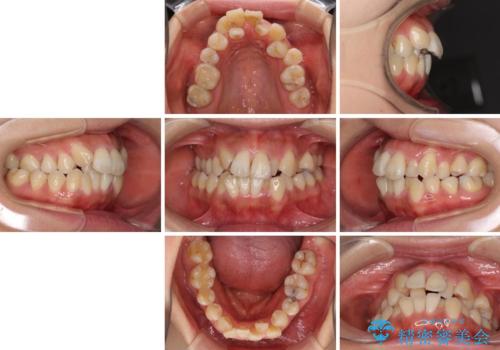

- 上顎の著しい叢生と奥歯の咬みにくさを気にして来院された患者様です。

骨格的に上顎は狭く、下顎は右側にシフトしていたため、右側臼歯はクロスバイトとなっていました。

上顎骨を急速拡大装置により拡大し、ワイヤー装置による抜歯矯正治療を行うこととしました。